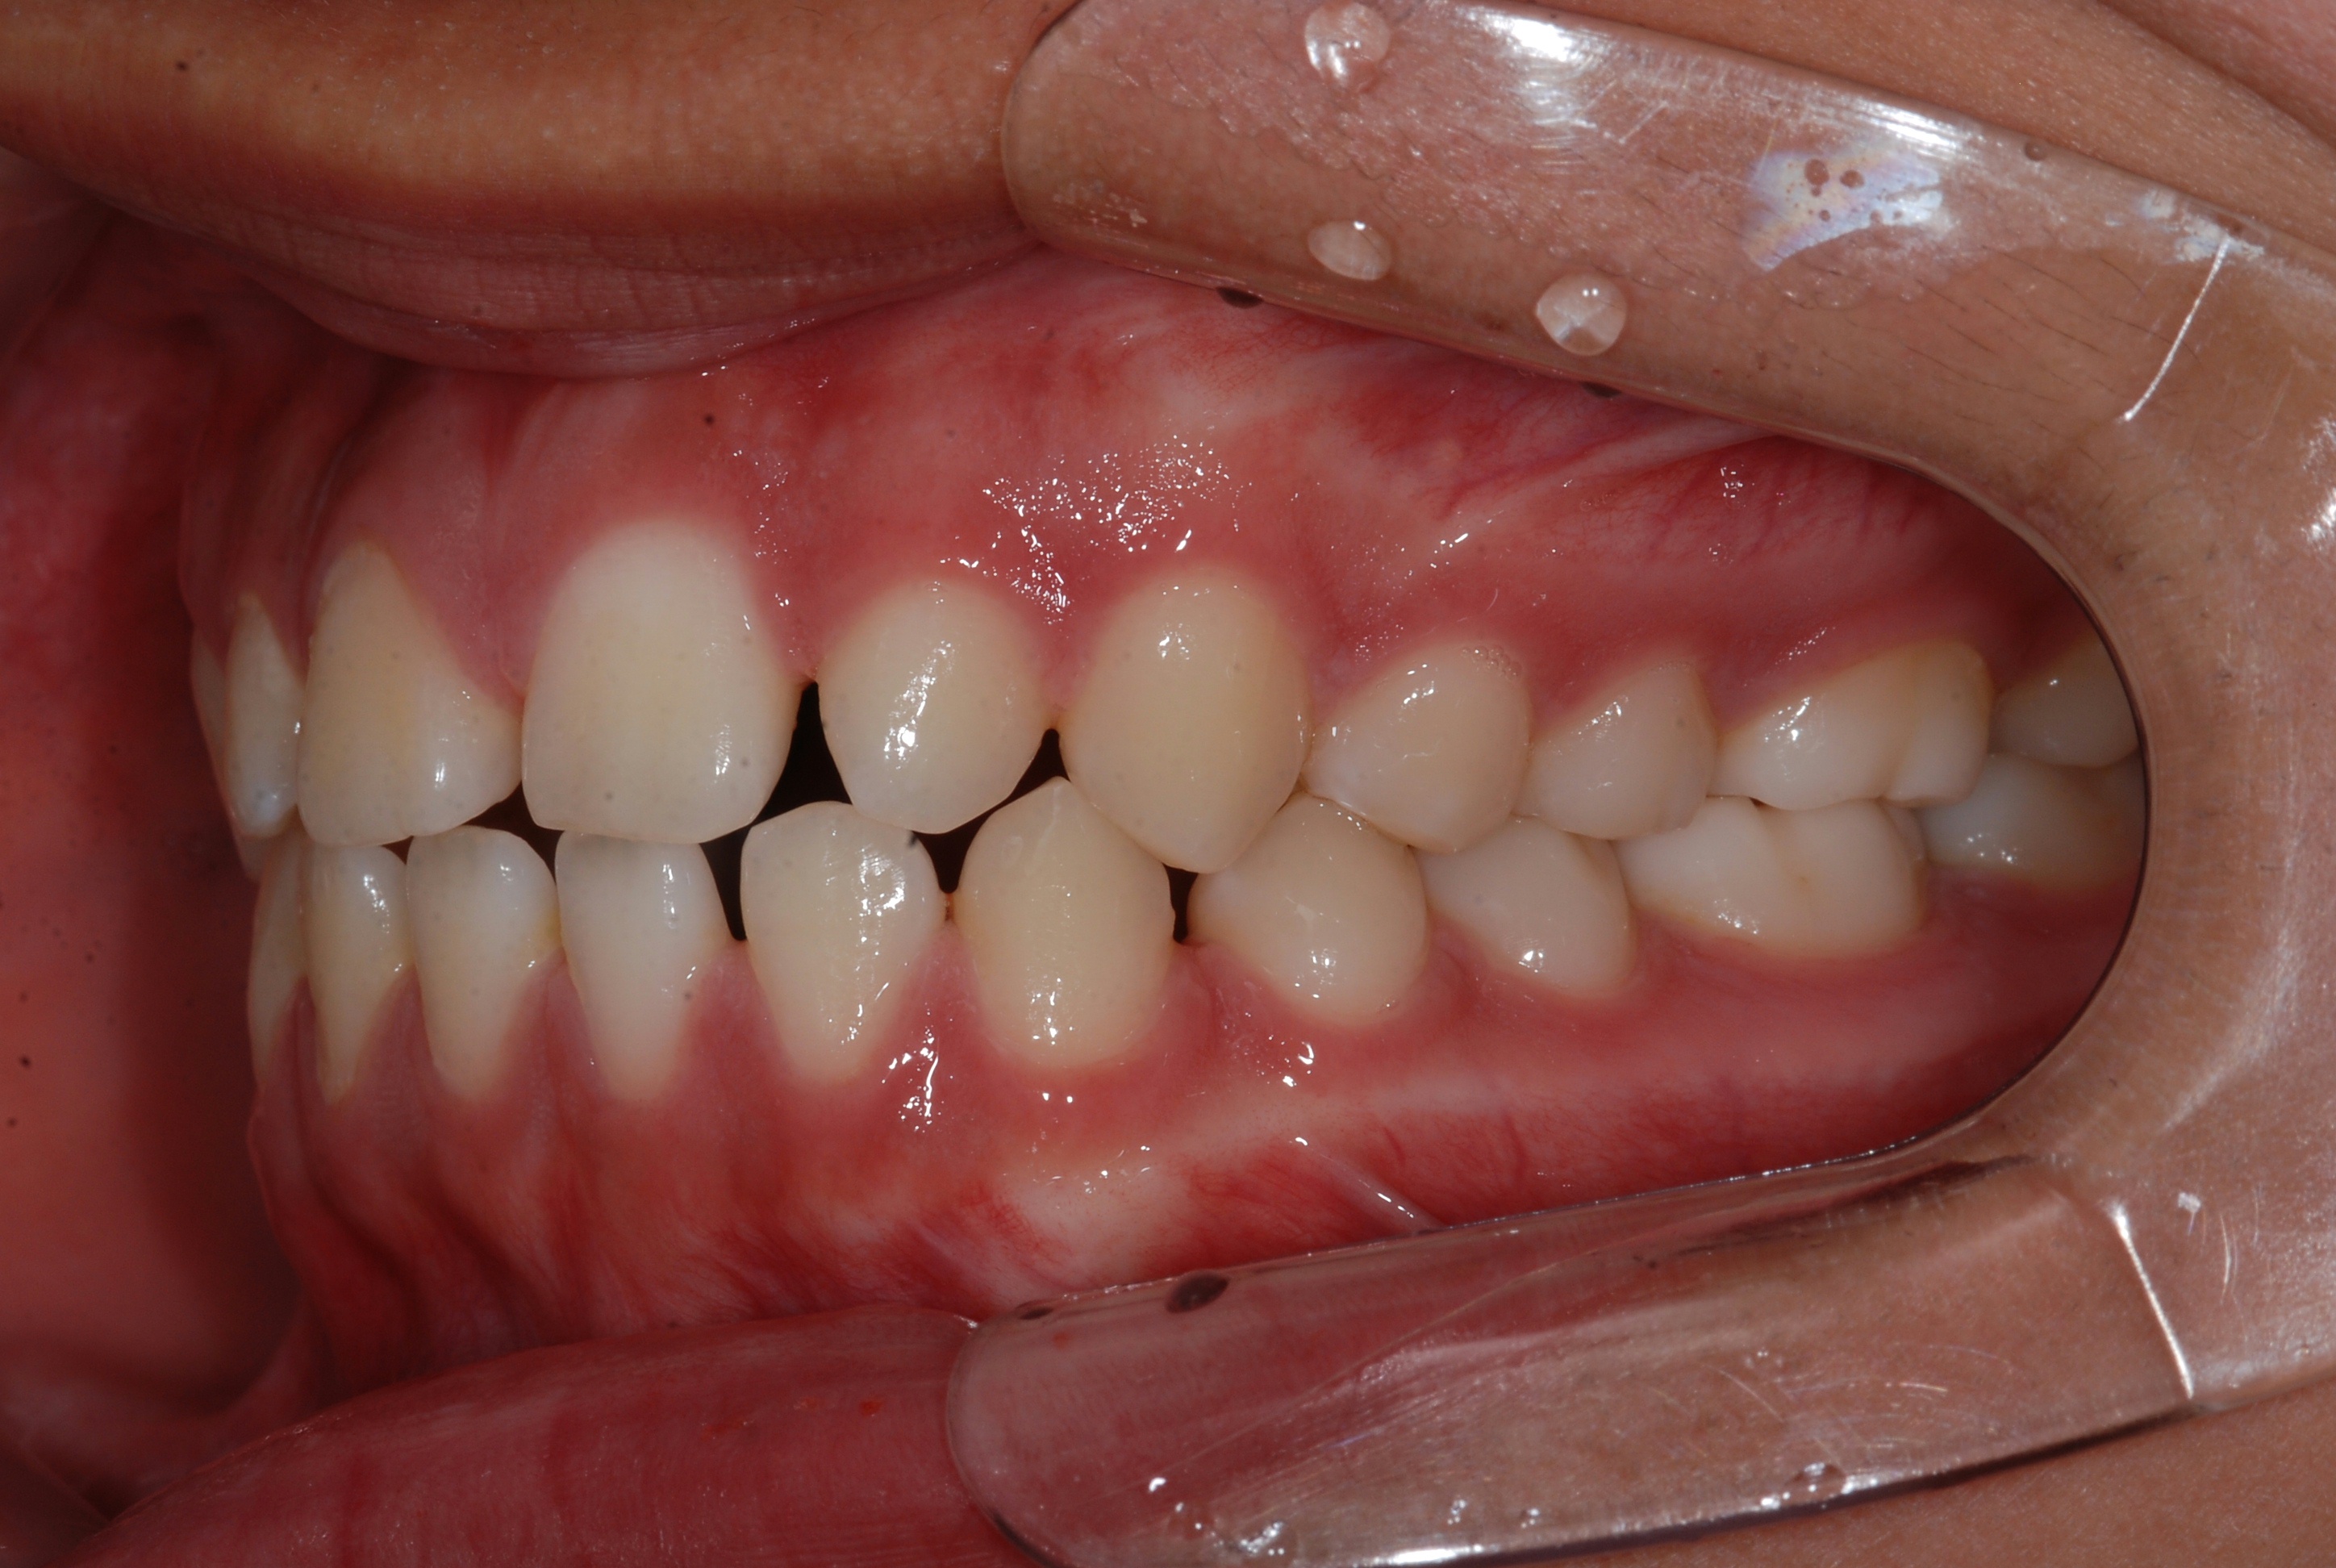

치료 전 사진입니다.